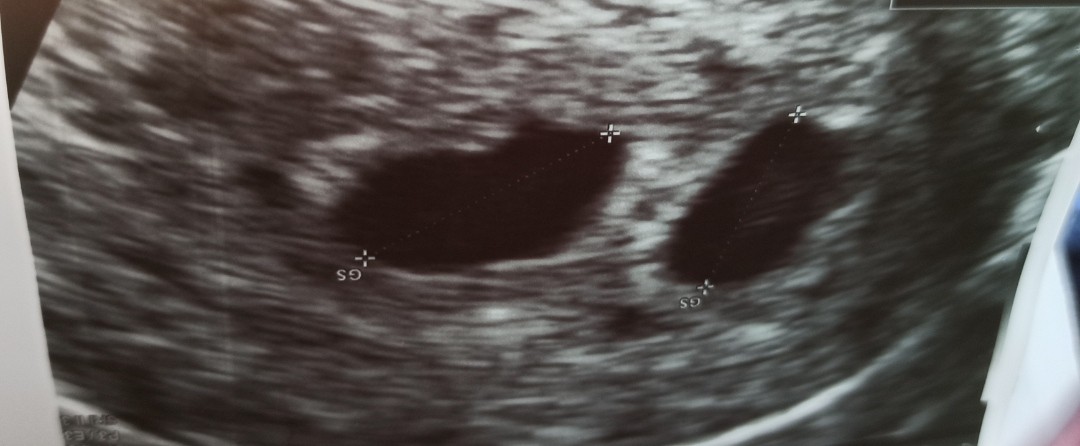

Na pewno statystycznie większa szansa, że będą dwujajowe, ale jednak pęcherzyki bezpośrednio do siebie przylegają więc ja bym nie miała pewności 100%. Dla porównania u mnie wyglądało to tak- zobacz że pęcherzyki są mocno oddalone i tu jest pewność że ciąża dwujajowa ( procedura in vitro-miałam podawane dwa zarodki podczas transferu)

• IMG_20220729_102148.jpg

IMG_20220729_102148.jpg

77,6 KB · Wyświetleń: 121